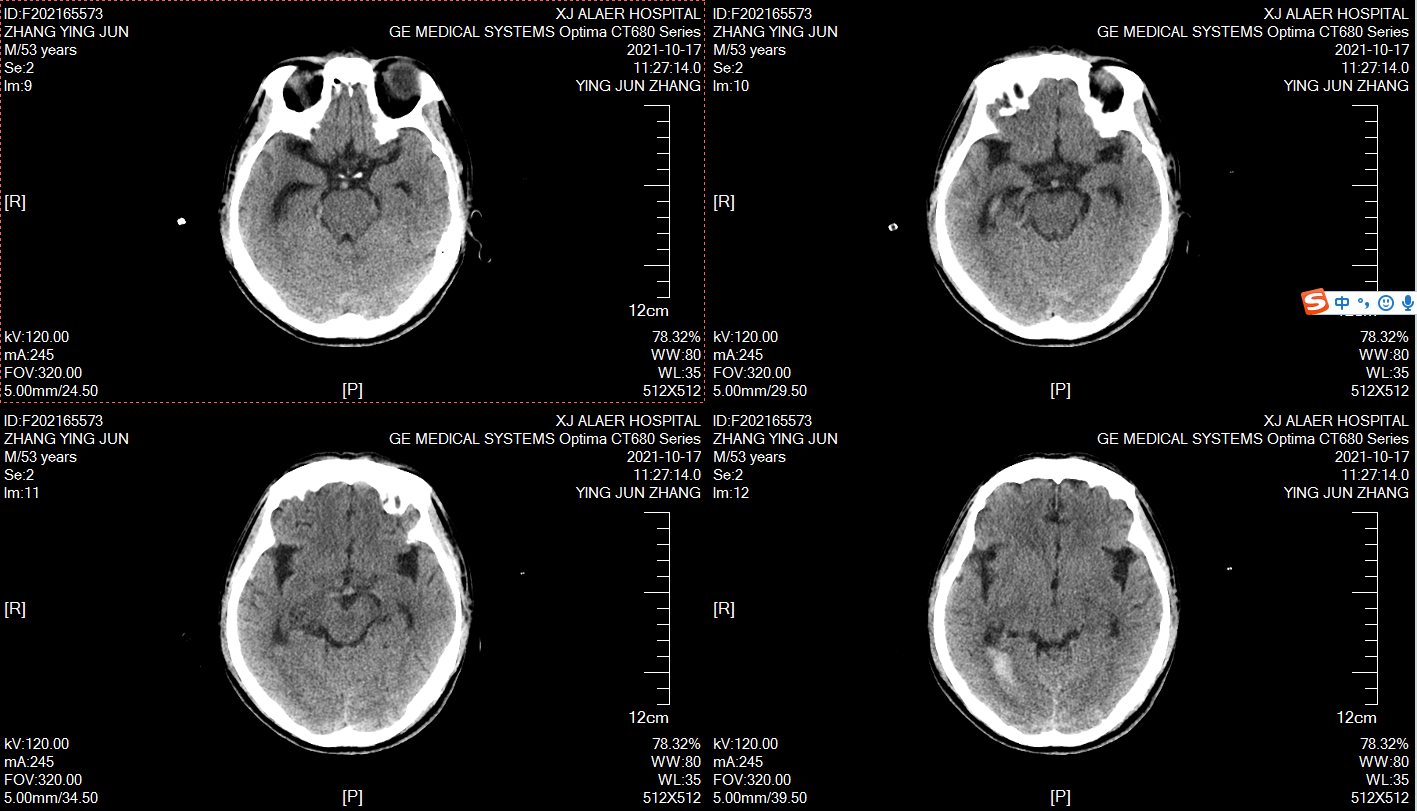

术前颅脑CT,男性,59岁,突发意识不清2小时,目前昏迷,GCS6分,右侧瞳孔4mm,左侧瞳孔2mm,脑室出血,烟雾病!